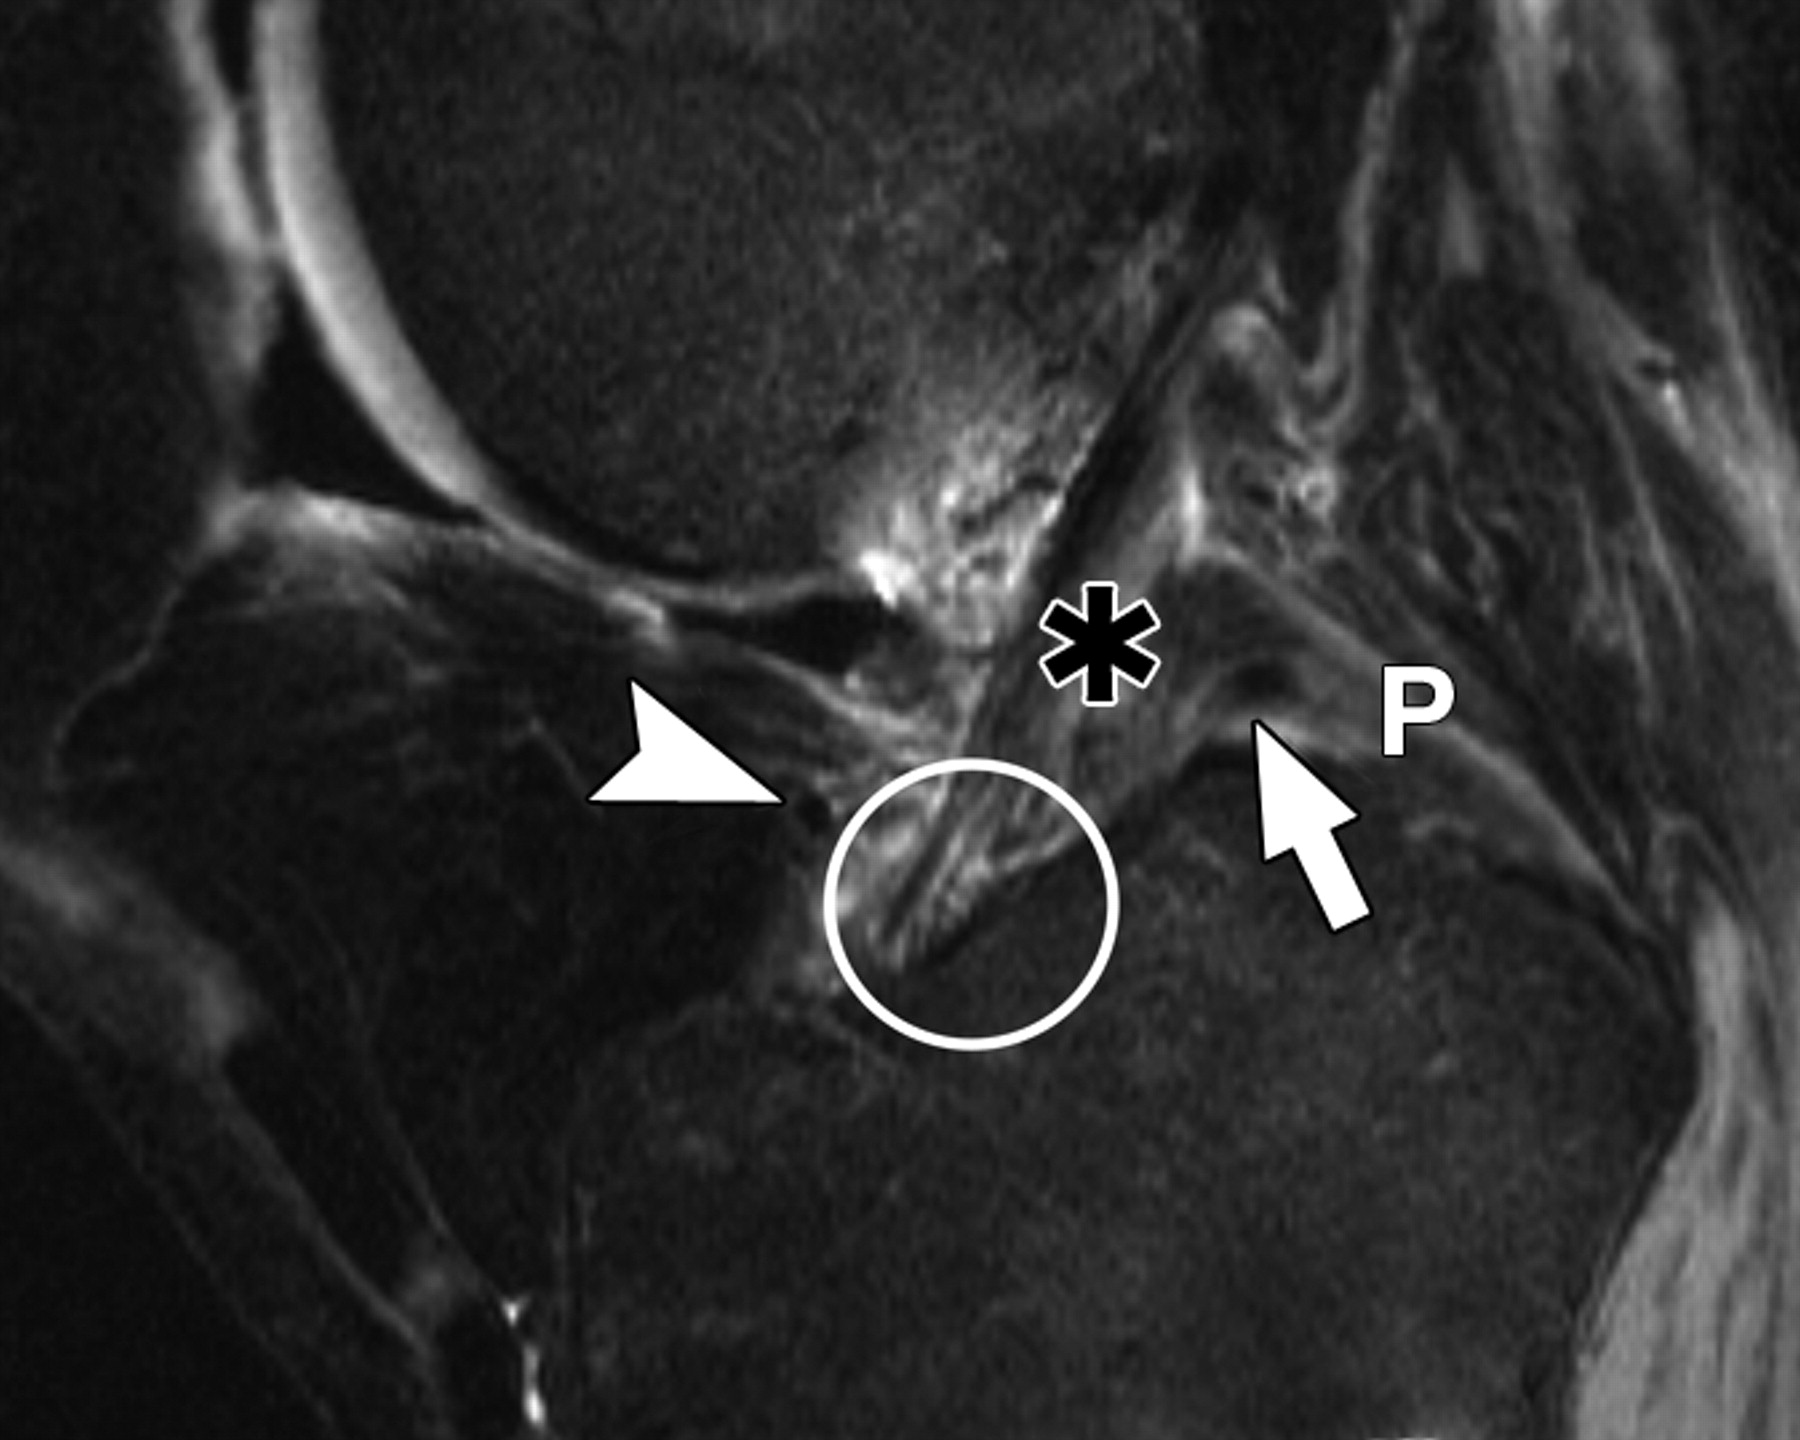

c72f940e7a2b62d20ba7c9ccc9eff2c3.jpeg

图3B-51岁女性。

膝关节的中等加权、脂肪饱和、快速自旋回波(TR/TEeff,3,700/29)3-T MR图像显示了膝关节前根、前交叉韧带(ACL)和膝横韧带的解剖关系。相对于A的后部冠状位MR图像显示内侧胫骨结节(MT)外侧斜面上外侧半月板(LM)前根的附着点(圆圈)接近ACL胫骨附着点(星号)。P =后交叉韧带,MM =内侧半月板。